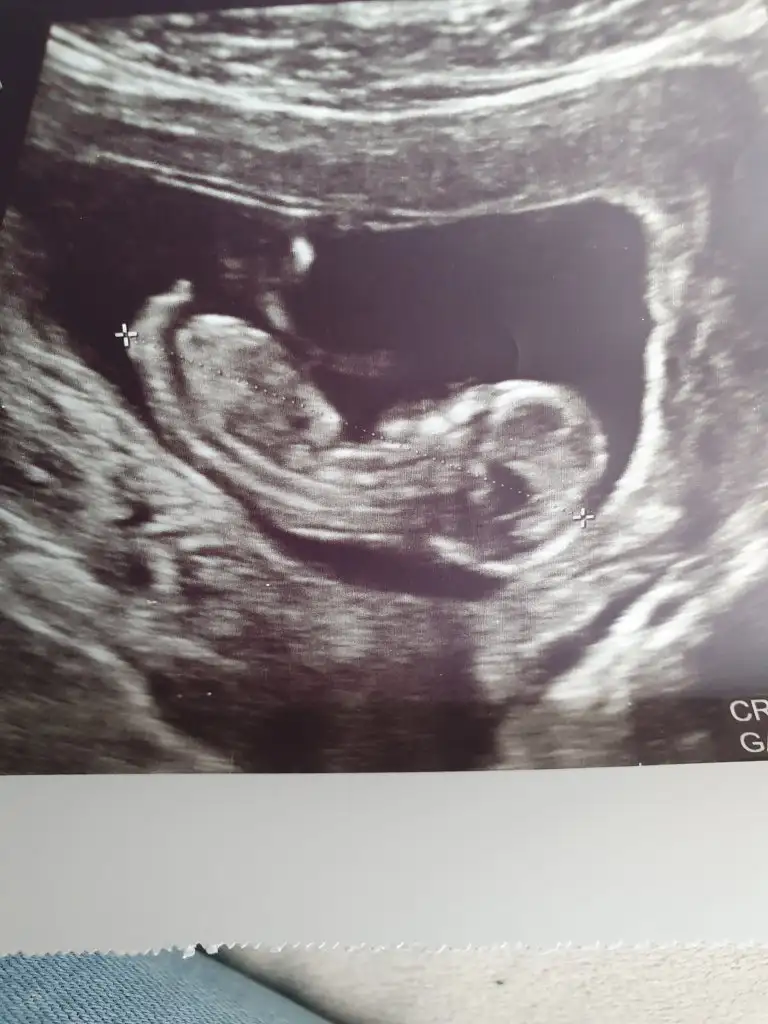

Arkası dönük yaabize de bakar mısınızzzzz:) C catloverrrr

Kesin kız şüphem yokbenim bebeğimle aynıı görünüyor benimki büyüdü artık netleşti